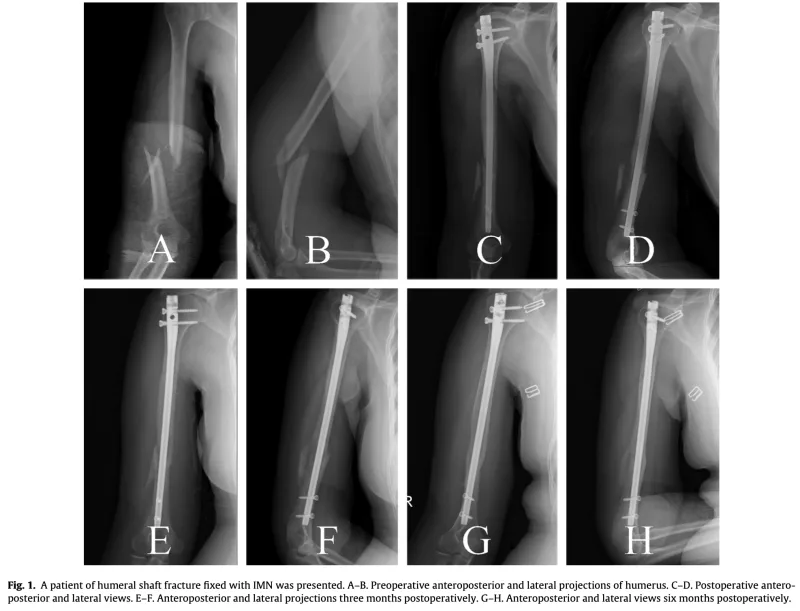

13時半からは上腕骨骨幹部骨折に対する手術.

上腕骨の中央部を骨折した超高齢患者さんに対して, 骨内にチタン合金製の髄内釘を挿入し固定しました. 骨粗鬆症が強く, スクリューの効きがやや弱めでしたが, 手術は予定通り約1時間で無事終了しました.